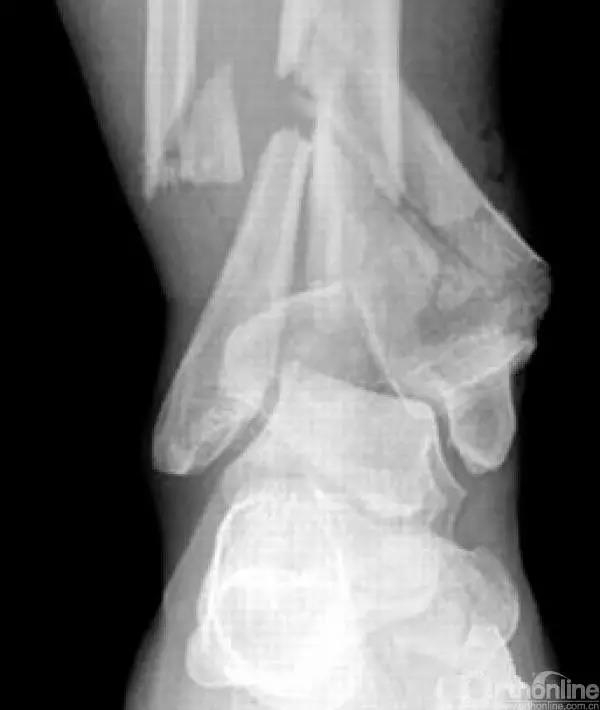

Pilon骨折为发生于胫骨远端并累及关节面,由垂直暴力合并或不合并扭转暴力导致的骨折,常表现为干骺端的压缩和关节面的粉碎。它是踝部的复杂骨折,以高能量损伤、不稳定、软组织损伤严重为特点。

Pilon骨折手术入路选择原则一般取决于最适合进行关节面复位的入路。cole在2013年jot发表的文章描述了pilon骨折的骨折线图根据多例病例汇总到一起,颜色越深则越骨折线经过的可能性越大。

他将pilon骨折大致的骨块进行了分类,分别为后、前内、前外三个骨折块。Pilon骨折的入路一共有5个,前内、前正中、前外、后内、后外。